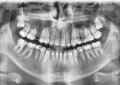

Мне 65 лет. Слева на верхней челюсти был мост на 4-е зуба (3-ий зуб и 6-ой свои под коронками).

2 месяца назад образовался флюс (гранулема под 3-им зубом) и зубы удалили. Доктор говорит, имплантация проблематична — низко дно гайморовой пазухи и кости мало.

Опасен ли синус-лифтинг в таком случае? И какой хоть и съемный протез можно сделать на одну сторону, например, поставить имплантат на место 3-го и за него зацепить остальные 3 зуба?

Синус-лифтинг операция по увеличению объемов костной ткани. Ее как раз проводят при близком расположении пазухи. В идеале рекомендуется проведение синус-лифтинга, установка двух имплантов с последующей фиксацией мостовидного протеза.